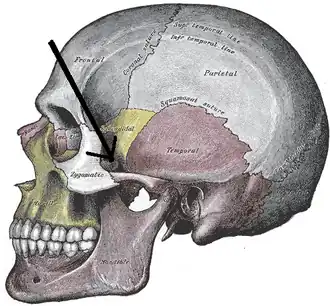

In anatomy, the zygomatic arch (colloquially known as the cheek bone), is a part of the skull formed by the zygomatic process of the temporal bone (a bone extending forward from the side of the skull, over the opening of the ear) and the temporal process of the zygomatic bone (the side of the cheekbone), the two being united by an oblique suture (the zygomaticotemporal suture);[1] the tendon of the temporal muscle passes medial to (i.e. through the middle of) the arch, to gain insertion into the coronoid process of the mandible (jawbone).

The zygomatic process of the temporal arises by two roots:

- an anterior, directed inward in front of the mandibular fossa, where it expands to form the articular tubercle.

- a posterior, which runs backward above the external acoustic meatus and is continuous with the supramastoid crest.

The upper border of the arch gives attachment to the temporal fascia;[2] the lower border and medial surface give origin to the masseter.